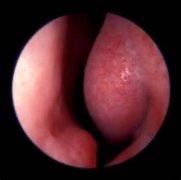

患者信息: 王勇 男 47 症状描述: 鼻塞、 ..[查看全文]